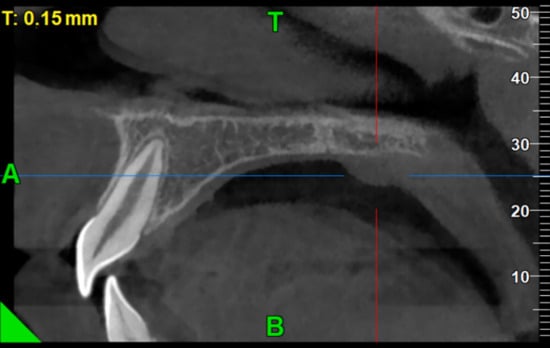

2. Case Presentation